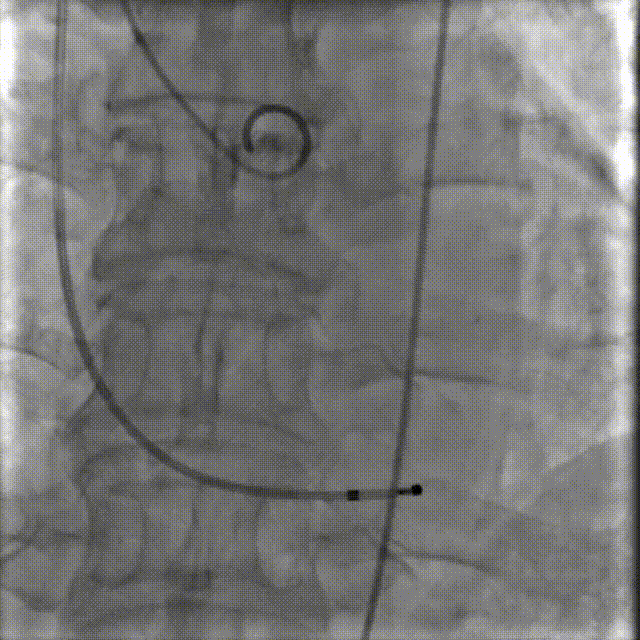

李有金教授 宁夏回族自治区人民医院 “随着人口老龄化加剧,主动脉瓣狭窄患者数量逐年增多,其中高龄、合并多种基础疾病的复杂病例占比不断提升。经导管主动脉瓣置换术(TAVR)作为微创治疗技术,已成为此类患者的重要治疗选择。对于高龄、有恶性肿瘤病史的患者而言,手术的安全性、微创性与长期疗效同等重要,既要最大程度降低手术创伤与并发症风险,也要确保瓣膜的耐用性与患者术后生活质量。 全球首款预装干瓣ProStyle A®的临床应用,为复杂病例治疗提供了全新解决方案。该瓣膜无需术中戊二醛冲洗,大幅缩短了手术操作时间,尤其适合高龄、心功能欠佳的患者。其独特的抗钙化工艺与优化的瓣架设计,既保证了瓣膜的长期耐久性,又能有效规避冠脉风险,为患者的“全生命周期管理”奠定了坚实基础。” 病例简介 现病史:患者半月余前突发抬头时一过性头晕,持续数秒钟,每日发作3-5 次,伴天旋地转感,症状可自行缓解。2025年12月12日就诊于外医院,心脏彩超提示“主动脉瓣狭窄(重度)并关闭不全(轻度),左室壁增厚,升主动脉增宽,左心室收缩功能正常,舒张功能减退”,建议转上级医院诊治。为求进一步治疗,患者就诊我院,门诊以“主动脉瓣狭窄”收住入院。 既往史:胃癌,胃大部切除术后五年。 临床诊断:“1.主动脉瓣狭窄伴有关闭不全(重度狭窄伴轻度关闭不全);2.主动脉瓣钙化;3.肥厚性非梗阻性心肌病;4.心功能不全;心功能III级(NYHA分级);5.升主动脉扩张;6.胃恶性肿瘤个人史” 术前CT评估显示:Type-1型二叶瓣,R-N钙化粘连,瓣叶重度钙化,主要分布在无冠窦瓣叶游离缘、R-N对合缘粘连处及右冠窦基底部;钙化积分933.2mm³;主动脉瓣环直径26mm,LVOT 27.6mm;双侧瓣叶开口高度可,左冠开口高度22.0mm,右冠开口高度20.0mm;主动脉水平夹角57.7°,左室内径偏小;主动脉弓部75.1°锐角弓;外周入路无明显迂曲及钙化,双侧股动脉内径可,右股中分叉。 手术策略 右侧股动脉为主入路,左侧为辅助入路,20F大鞘,股骨头中段穿刺;预装金仕生物 ProStyle A® AV26瓣膜,备29瓣膜,22mm球囊预扩;初始定位对齐瓣环上5mm超高位释放,释放过程中使瓣膜自然下滑至工作位,最终理想位置零位,利用瓣上锚定与封堵,规避冠脉风险;术前适当补液; 手术过程 Step1:主动脉根部造影; 主动脉根部造影 Step2:使用“先瑞达”22mm球囊预扩,无腰无漏,冠脉充盈良好; 球囊预扩 Step3:将ProStyle A®预装干瓣送至目标位置,初始定位后缓慢释放,观察瓣膜自然下滑至理想工作位; 定位 释放至工作位观察 Step5:瓣膜完全释放后,再次造影,显示瓣膜位置、形态良好,导管测平均跨瓣压差由术前60mmHg-降至1mmHg,冠脉血供正常; 最终造影 Step6:术后即刻超声监测,人工瓣膜位置固定,瓣叶启闭无受限,瓣周少量反流。 术后患者病情稳定,已于一周后出院。 结语 作为宁夏回族自治区心血管疾病诊疗的核心高地与区域医疗中心建设的标杆单位,宁夏回族自治区人民医院始终坚守“敬佑生命、救死扶伤”的医者初心,以“技术引领、学科兴院”为发展理念,在心脏大血管领域持续深耕,构建了集“精准评估-个性化方案-微创治疗-全程康复”于一体的诊疗体系。此次西北首例ProStyle A®预装干瓣植入手术的圆满成功,不仅是医院在复杂结构性心脏病介入治疗领域的又一突破性成果,更彰显了医院在引进前沿技术、转化创新器械、服务复杂重症患者方面的责任与担当。 Prostyle A®预装干瓣——助力临床最优化解决方案: 预装干瓣 便捷顺安:金仕生物专利抗钙化技术运用纳米技术去除组织内的细胞碎片和磷脂,封闭游离醛基,从根本上阻断了瓣膜钙化的多项因素,显著提升了瓣膜的耐久性;同时,相比较传统戊二醛保存方式,干式存储最大限度的保留心包的亲水亲油平衡,还原组织天然曲柔性,进一步保障了瓣叶开合,保证长期耐久性; 平衡径向支撑力:Prostyle A®瓣架网孔比例按照病例解剖结构的特殊设计,使瓣膜在狭窄最重的地方良好的撑开,同时避免对瓣环及周边组织的过度压迫,有效降低传导阻滞风险; 精准释放:底部桶状设计更易迅速锚定,协同释放张力小,助力最终精准释放; 过弓柔顺:较细的输送系统直径+亲水涂层,显著提升输送系统通过性,有效减少血管并发症的发生,内连鞘版本最小尺寸等效14F大鞘; 专家简介 李有金 宁夏回族自治区人民医院(点击查看专家详细简历) · END ·